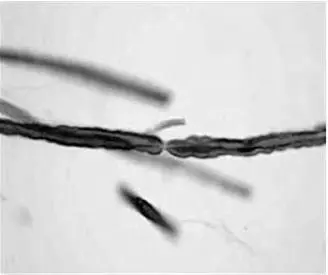

Миелин.Значительная часть аксонов заключена в липопротеиновую оболочку, которая начинается на некотором расстоянии от тела клетки и заканчивается на расстоянии 2 мкм от синаптического окончания (рис. 1.5). Нервные волокна, окруженные такими оболочками, называются миелинизированными. Миелиновые оболочки содержат холестерин, фосфолипиды, некоторые цереброзиды и жирные кислоты, а также белковые вещества, переплетающиеся в виде сети (нейрокреатин). Химическая природа миелина периферических нервных волокон и миелина центральной нервной системы несколько различна. Это связано с тем, что в центральной нервной системе миелин образуется клетками олигодендроглии, а в периферической – леммоцитами. Эти два вида миелина отличаются по своим антигенным свойствам. Миелиновые оболочки нервных волокон не сплошные, а прерываются вдоль волокна промежутками, которые называются перехватами Ранвье (рис. 1.6). У места окончания миелиновой оболочки на уровне перехвата Ранвье наблюдается некоторое сужение аксона, диаметр которого уменьшается на 1/3.

Рис. 1.5 . Аксон нейрона, заключенный в миелиновую оболочку

Рис. 1.6 . Миелинизированное нервное волокно в области перехвата Ранвье

Электронно-микроскопически миелин сформированной оболочки состоит из плотных пластинок толщиной около 0,25 нм, которые повторяются в радиальном направлении с периодом 1,2 нм. Между ними находится светлая зона, представляющая собой сильно насыщенное водой пространство между двумя компонентами биомолекулярного липидного слоя. Это пространство доступно для циркуляции ионов. Миелиновая оболочка обеспечивает изолированное, бездекрементное (без снижения амплитуды потенциала) и более быстрое проведение возбуждения вдоль нервного волокна. Имеется прямая зависимость между толщиной этой оболочки и скоростью проведения нервного импульса.